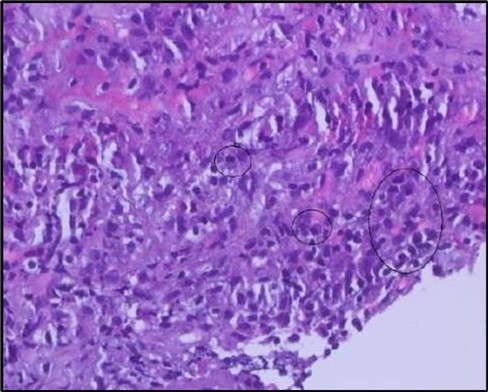

Two weeks post-surgery, the left eye showed significant healing, with a small conjunctival granuloma and vascularization at the ulcer margins. The cornea was clear with a central leading edge nasally, deep and quiet anterior chamber and clear lens. VA 6/6 bilaterally and IOP normal. Histopathology of excised conjunctiva showed non-keratinized squamous epithelium with superficial erosions, stromal elastosis, hemorrhage, and inflammatory infiltration, but no signs of granulomatous disease, malignancy, or viral evidence, findings consistent with idiopathic localized inflammatory process. The patient reported significant relief and satisfaction post-surgery, resuming normal activities. Treatment continued with oral prednisolone 25 milligrams every other day, tobramycin-dexamethasone ointment twice daily, and preservative-free artificial tears four times daily Figure 4, Figure 5a, Figure 5b, Figure 5c, Figure 5d.

Figure 5a.OS, Hematoxylin and eosin (H&E) stained section of the corneal specimen demonstrating full-thickness epithelial loss with underlying stromal necrosis.

Figure 5b.OS, High-power H&E view showing dense inflammatory infiltration within the corneal stroma composed predominantly of lymphocytes and numerous plasma cells (circles highlight plasma cells).

Histopathological examination revealed a dense infiltration of CD138-positive plasma cells within the excised conjunctival tissue (Figure 5b, Figure 5c, Figure 5d). This finding supports an antibody-mediated immunopathogenesis in Mooren’s ulcer, consistent with Type II and Type III hypersensitivity mechanisms described in the literature 20, 21. The prominent presence of CD138- positive plasma cells provide a clear pathological rationale for conjunctival resection, as excision of the immunologically active perilimbal conjunctiva effectively removes the local 'factory' of autoantibodies that drive corneal stromal destruction, thereby halting ongoing tissue damage 21.